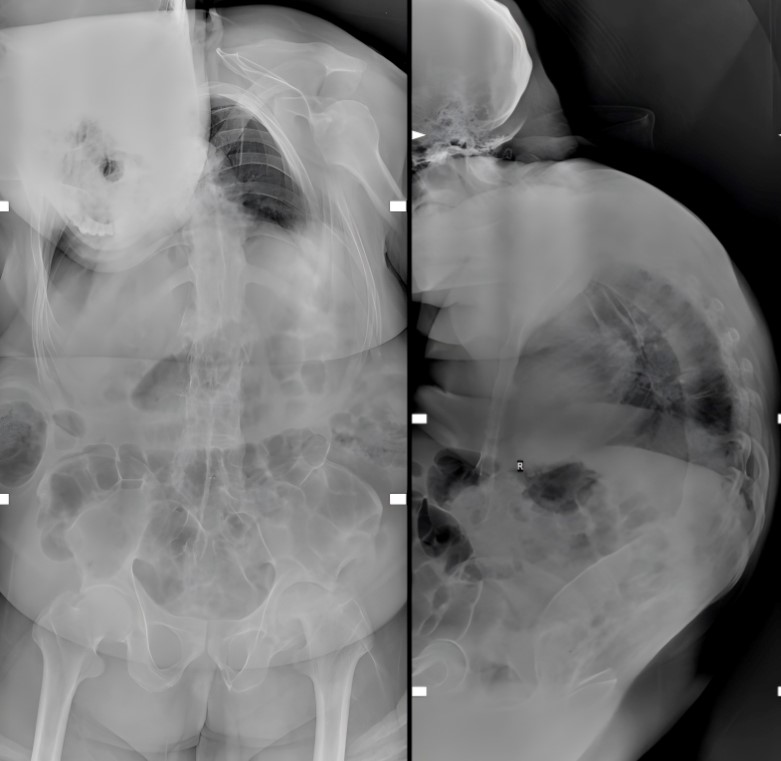

患者为57岁男性,因胸椎骨折、胸部脊髓损伤入院,需紧急手术固定以挽救脊髓功能。然而,患者长达二十余年的强直性脊柱炎病史,已导致其脊柱呈“竹节样”改变,严重后凸无法平卧,颈部及下颌关节活动严重受限,为手术体位的安置与麻醉气管插管带来了极大挑战。

术前详细评估显示,患者头颈活动度为0度,张口度不足3cm,甲颏间距仅4.5cm,颏胸距离为6cm(正常>12.5cm),Mallampati分级达到III级,属于典型的“困难气道”。若采用常规方法进行气管插管,极易出现声门暴露困难、插管失败等情况,甚至可能导致缺氧、牙齿损伤、气道损伤等严重并发症,风险极高。